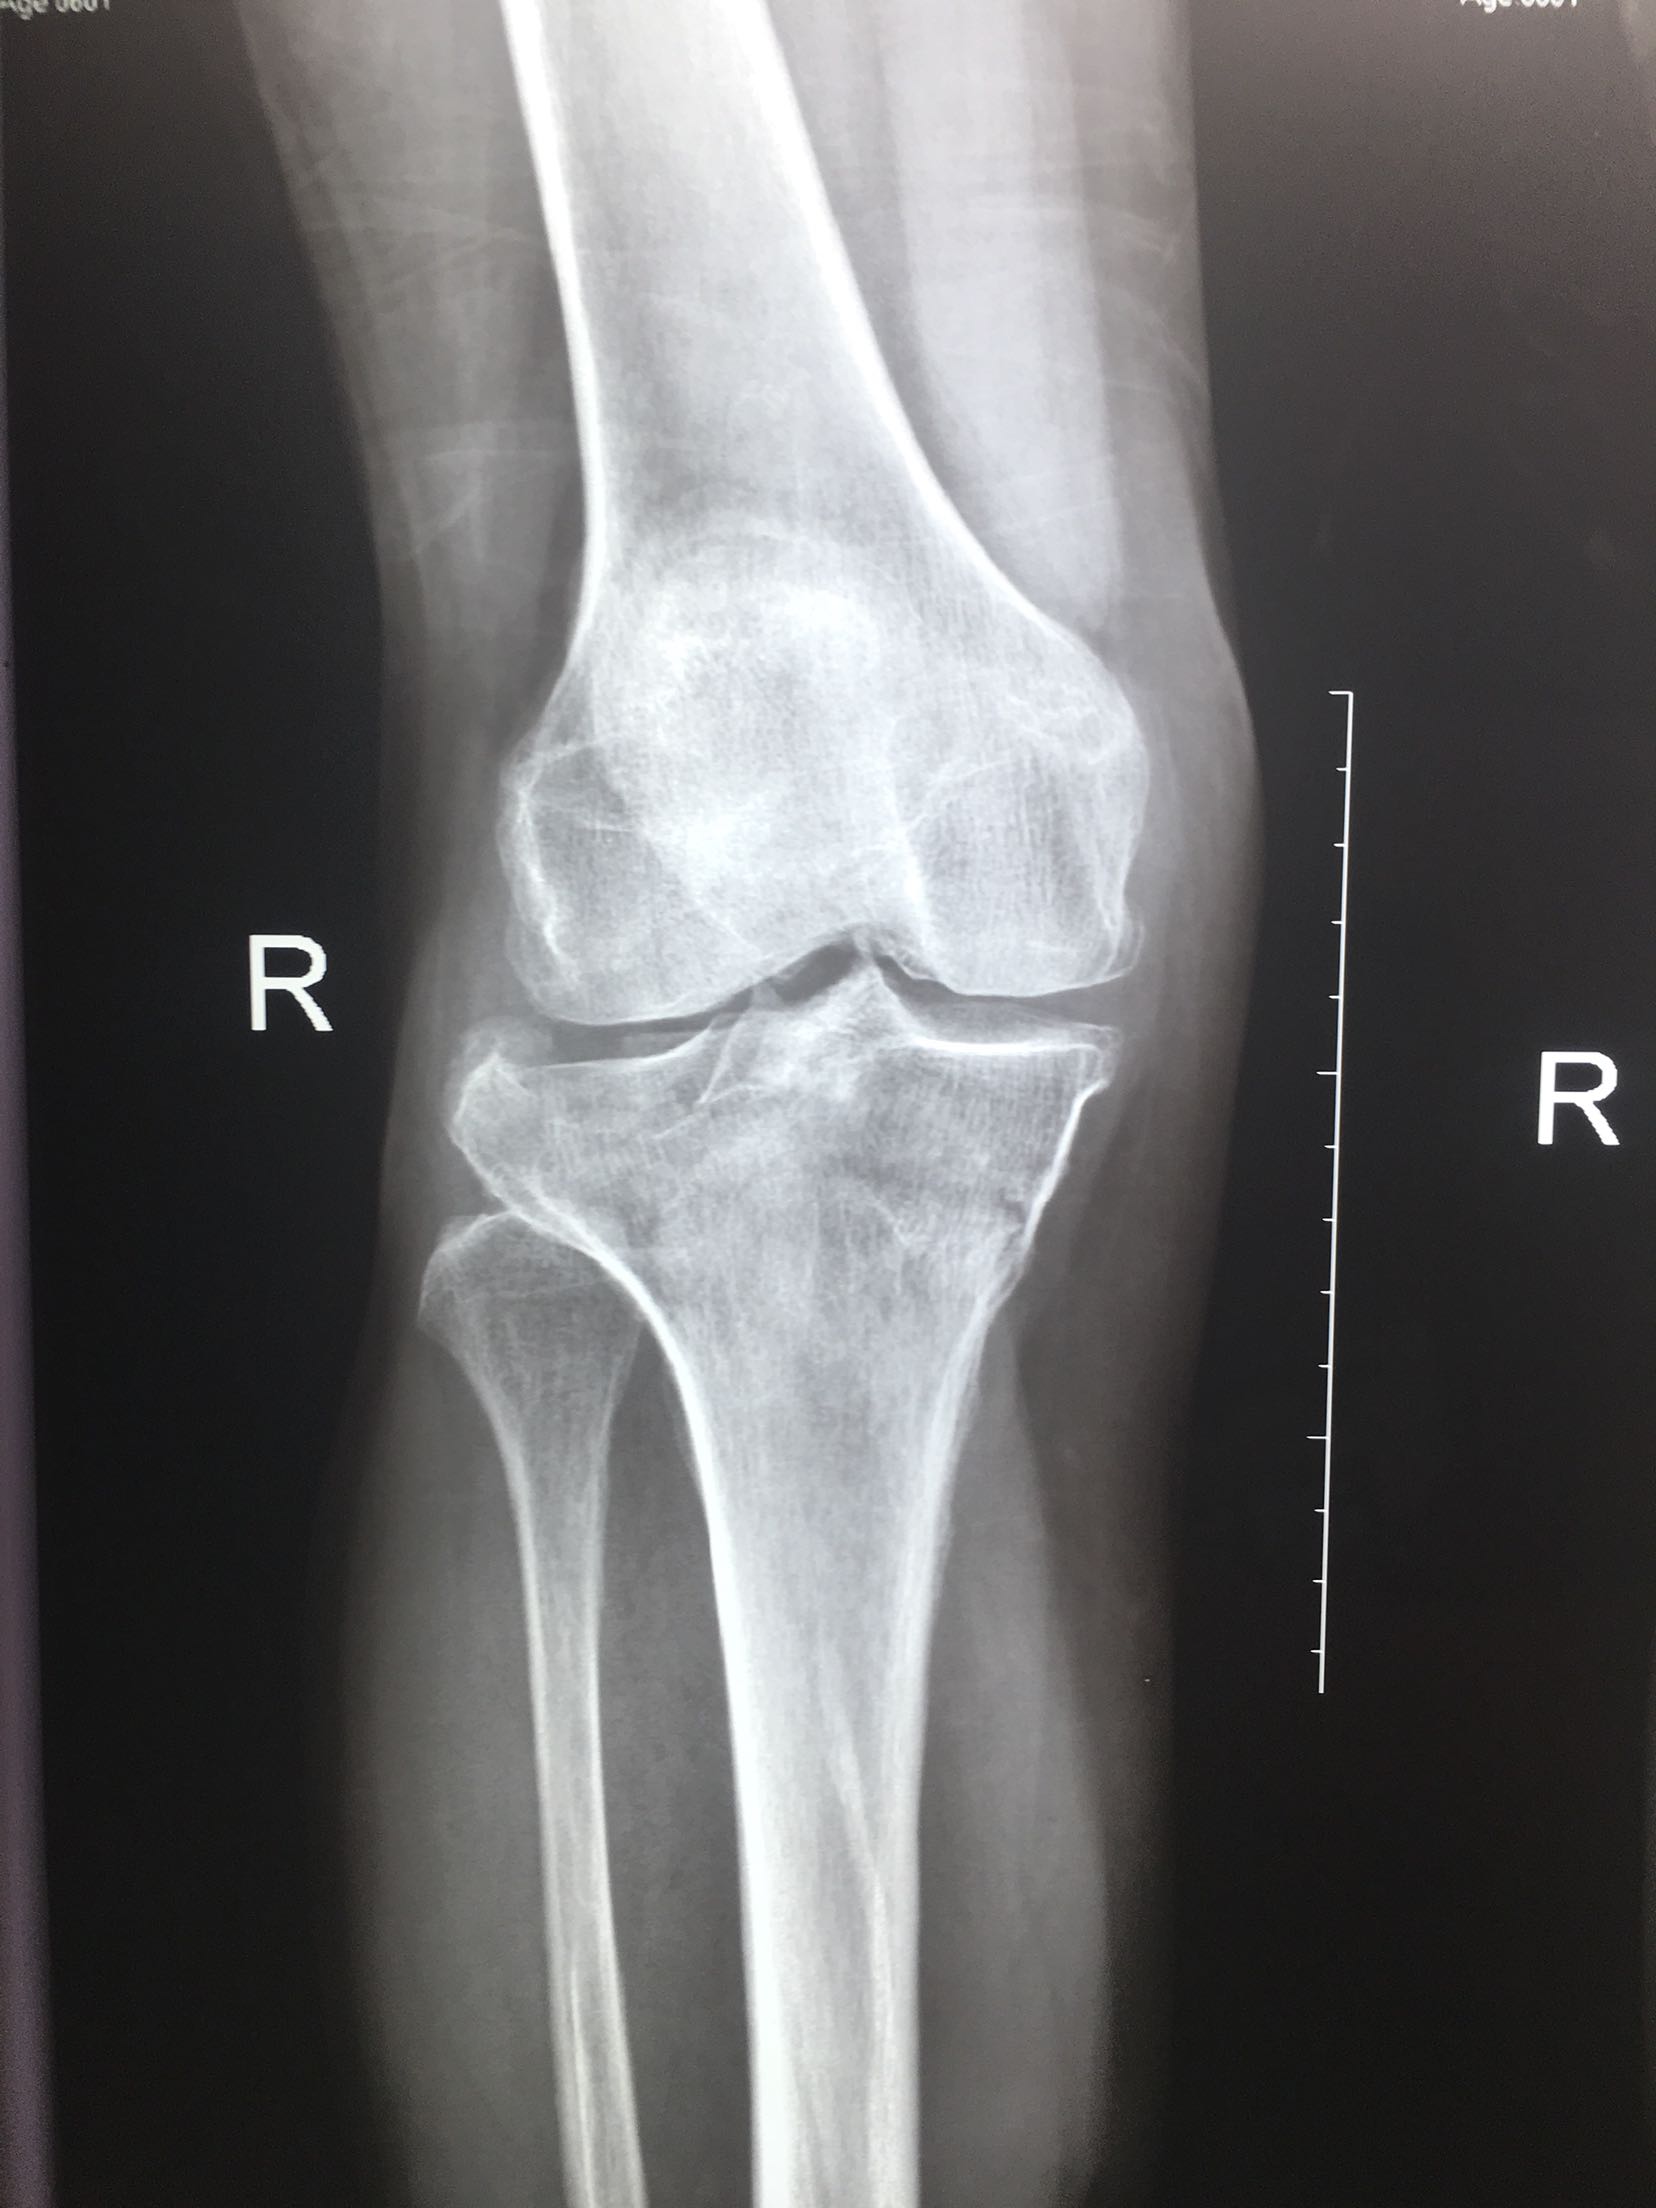

右胫骨平台骨折-医联

680x907 - 37KB - JPEG